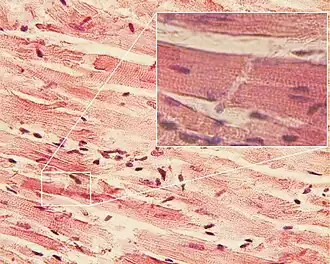

Tecido Muscular Estriado Cardíaco

O músculo cardíaco encontra-se apenas no coração.[7] Assim como o músculo esquelético, ele é estriado e, como o músculo liso, ele é uninucleado e seu controle é realizado pelo sistema nervoso autônomo.[7] As células do músculo cardíaco são cilíndricas e têm ramificações que permitem a elas se conectarem umas às outras.[7] Essas ramificações conectam-se por meio de áreas especializadas denominadas discos intercalares.[7]

As células do músculo cardíaco são muito menores do que as células do músculo esquelético e liso.[7] Esse músculo gera a contração e bombeia sangue para todo corpo.[7] As ramificações interconectadas das células do músculo cardíaco garantem que o bombeamento do coração seja feita de maneira coordenada[7]

Estrutura

As células musculares cardíacas são estriadas, ramificadas e involuntárias.[8] Suas células são unidas em uma rede contínua, e não há nenhuma camada que as separe.[8] As membranas das células adjacentes são fusionadas em locais denominados discos intercalados, um sistema de comunicação nas áreas fusionadas impede a contração independente de uma célula.[8]

Uma célula muscular cardíaca (cardiomiócito) possui cerca de 10 a 20 µm de extensão.[9] O citoplasma contém miofibrilas e mitocôndrias densamente agrupadas.[9] Essas fibrilas não correm estritamente paralela umas às outras, mas ramificam-se em um padrão complexo.[9]

As células musculares cardíacas possuem um núcleo centralmente localizado.[9] A estrutura do sârcomero é semelhante a estrutura do músculo esquelético.[9] Os túbulos T são maiores e ramificados, enquanto o sistema L é menor em relação a estrutura do músculo cardíaco.[9] Além disso, os discos intercalares conectam as células cardíacas mecânica e eletricamente.[9]

Os discos intercalares são encontrados exclusivamente no tecido cardíaco e possuem a função de transmitir os sinais de uma célula para outra, garantindo a sincronização da contração cardíaca e impedindo a separação dessas células durante o batimento cardíaco.[1] Nessas junções intercelulares encontram-se três especializações juncionais principais: zônula de adesão, desmossomos e junções comunicantes.[1]

Quando a célula recebe o sinal para se contrair, todas as células vizinhas são estimuladas e se contraem juntas produzindo o batimento cardíaco.[8]

O batimento cardíaco mantém um ritmo de cerca de 70 contrações por minuto, no entanto, a atividade de vários terminais nervosos podem levar o coração a aumentar ou diminuir o seu ritmo.[8] O músculo cardíaco requer um aporte contínuo de oxigênio para funcionar.[8] Se o suprimento de oxigênio for interrompido por apenas 30 segundos, as células musculares cardíacas começarão a morrer.[8]